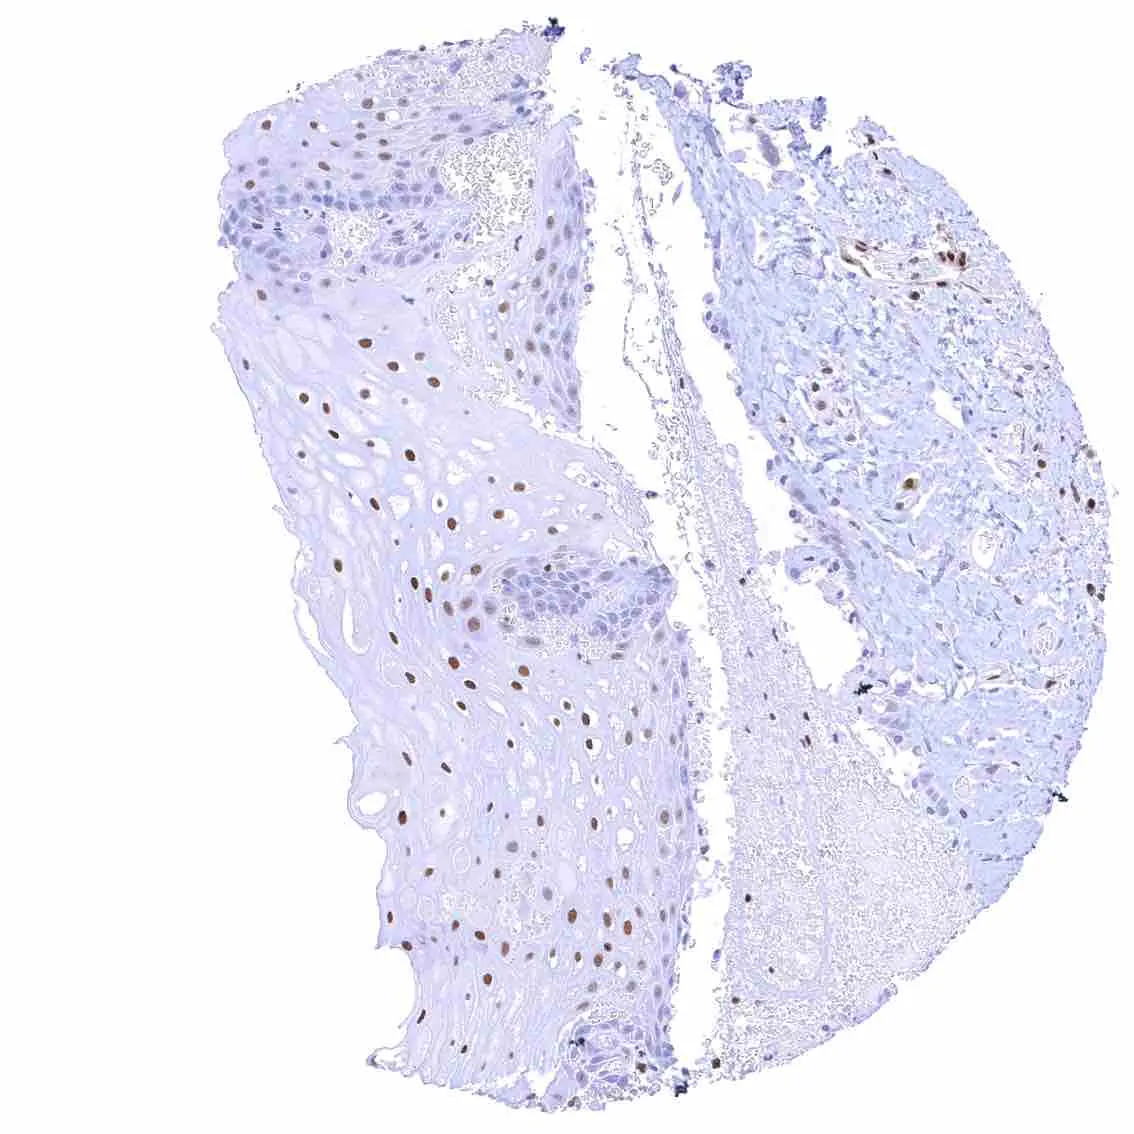

Skin – Moderate to strong nuclear p27 staining occurs in a large fraction of squamous epithelial cells and predominates in the more mature cell layers (top 50_ of the epidermis).

Skin, hairfollicel and sebaceous glands – Moderate to strong nuclear p27 staining in all cells of sebaceous glands.